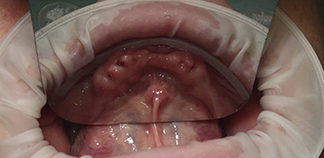

До лечения

Жалобы на отсутствие зубов.

Как лечили

Установлены шесть имплантов на верхней челюсти и четыре импланта на нижней. Зафиксированы постоянные коронки.

Лечащие врачи

МИРОШНИЧЕНКО Алексей Михайлович, БАЛЕВ Дмитрий Олегович